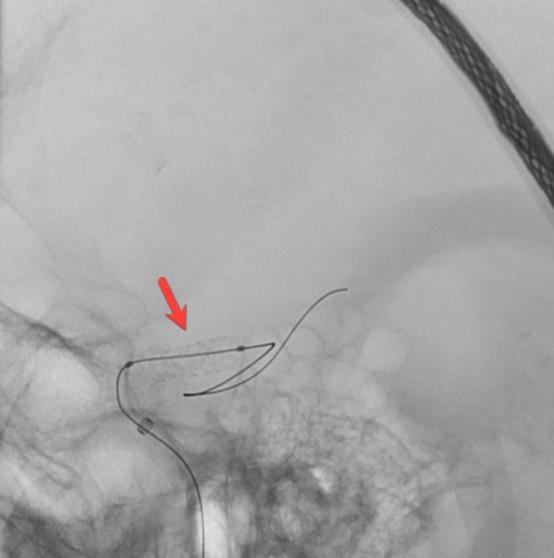

在转运的过程中,患者症状持续加重,完全失语、右侧肢体全瘫同时意识逐渐模糊。糟糕,一定是左侧颈内动脉闭塞后血流缓慢继发颅内血栓形成。时间就是大脑,为挽救李大哥的生命,民航总医院卒中团队高效运作起来,神经内科、血管介入科、麻醉科迅速完成了患者的转运、麻醉及造影。如术前所料,患者左侧颈内动脉C6段闭塞(图4、5),左侧大脑中动脉M2段血栓形成(图6)。一个一个环环相扣的动作,一个一个精细无间的配合,血管介入科团熟练的完成了取栓支架就位(图7)、取出大脑中动脉血栓、植入颈内动脉支架(图8)等一系列操作,成功的开通了血管,恢复了颅内的血流(图9、10)。

图6

图7

图8